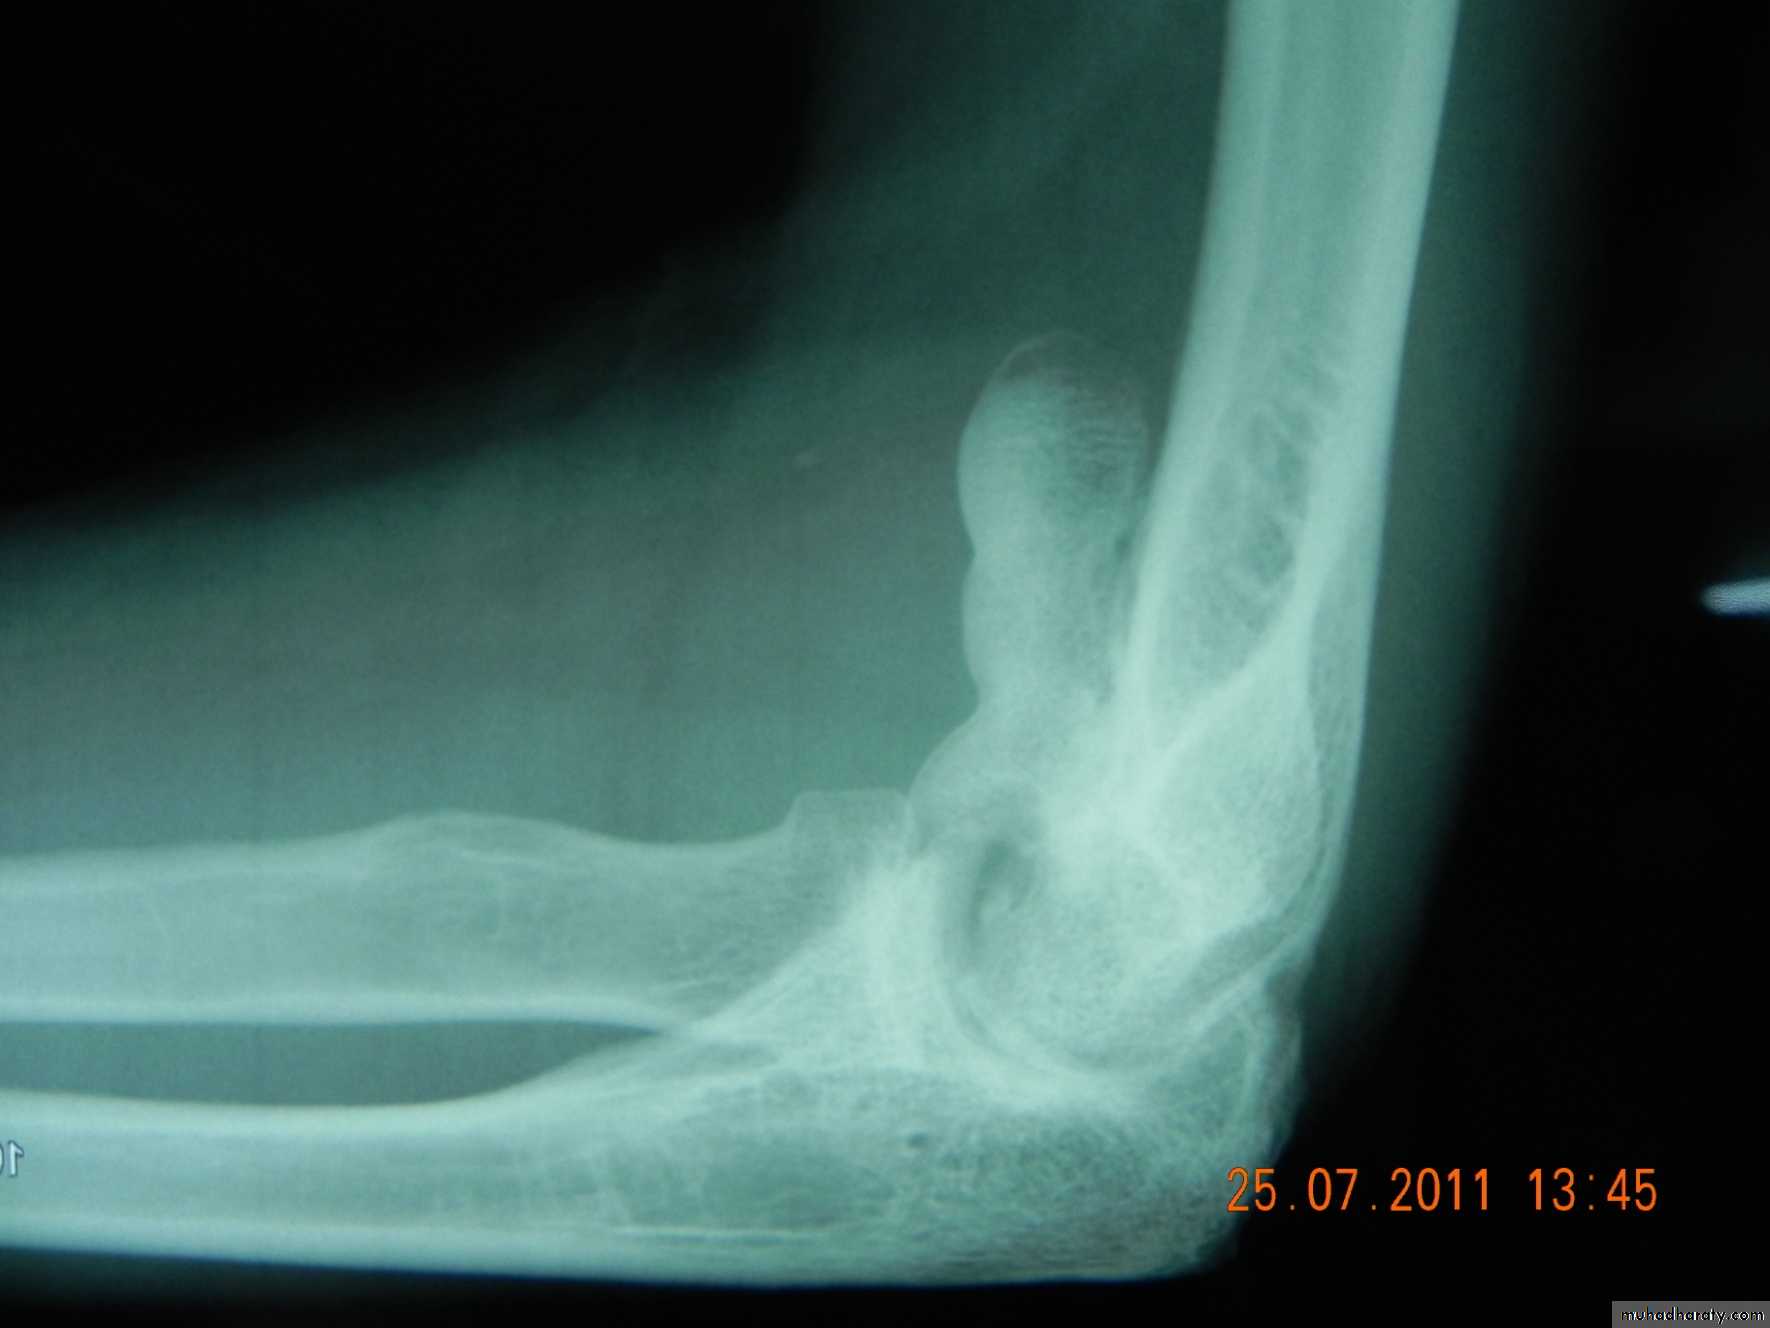

Joints

Shape:

Decreased joint space and oseophytes in osteoarthritis.

Dislocation or subluxation.

Density: increased in chondrocalcinosis, loose bodies…

Deformity;

Sudden; eg elbow dislocation,